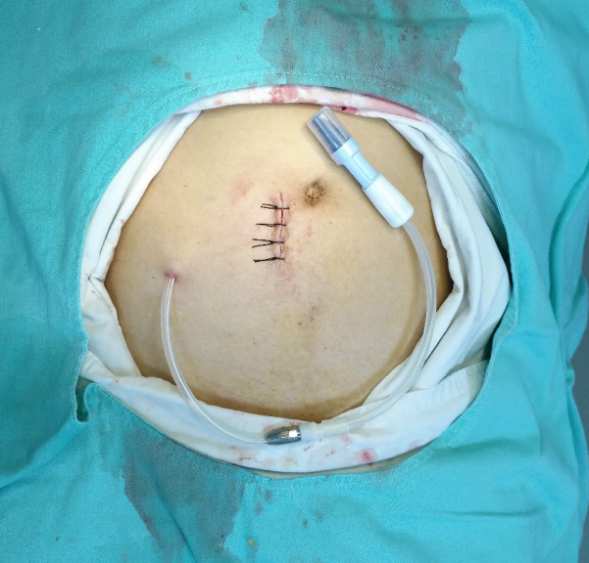

四、腹膜透析:

肾内科腹膜透析中心是广西较早开展腹膜透析的单位,是南宁市率先开展腹膜透析技术单位,南宁市居家自动化腹膜透析治疗体系建设示范中心单位,西南腹膜透析诊治联盟理事单位,南宁市首家成立规范腹膜透析专病门诊。2019年开展自动化腹膜透析治疗技术,是通过机器辅助完成透析的一种先进肾脏替代治疗手段,让尿毒症患者更好回归社会,提高患者生存率、生活质量。2023年推行互联网远程监控+居家自动化腹膜透析治疗模式,使得患者获得智能化、精细化、专业化的专科疾病全程管理,让尿毒症患者有能更合适的透析替代治疗选择。

科室设有腹膜透析病房、腹膜透析治疗室、腹膜透析培训室、腹膜透析专病门诊,常规开展腹膜透析(PD)、自动化腹膜透析(APD),自动化腹膜透析-远程管理技术(APD-RPM)等。在应用常规腹膜透析基础上,应用新型腹膜透析液:艾考糊精腹膜透析液、中性腹膜透析液等,可显著降低腹膜葡萄糖暴露和吸收量,有助于维持腹膜功能和患者的代谢特征,为腹透病人提供新选择。

图 腹膜透析置管